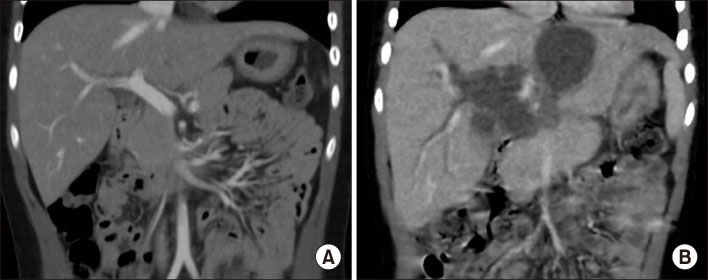

Fig. 4

Fig. 4 (A) CT scan taken at the 2nd admission shows the distal migration of endoscopic retrograde biliary drainage catheter with aggravated proximal biliary dilatation above the stricture site of mid-common bile duct. (B) Cholangiography during the operation.